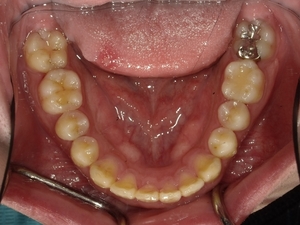

すきっぱ(空隙歯列)CASE7 2023.08.28 20代男性☆Before→After☆〇ご相談内容:前歯真ん中の隙間があいている〇矯正の種類:マウスピース型矯正「インビザラインGO」〇治療期間:19週間〇治療費用:44万円(税込) < すきっぱ(空隙歯列)CASE8すきっぱ(空隙歯列)CASE6 > ブログ記事一覧をみる